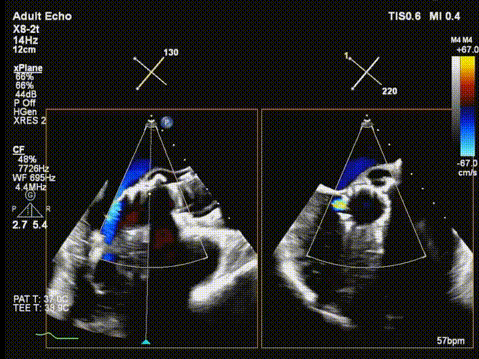

快速起搏下再次释放瓣膜至工作位,超声评估开口形态可,位置深度满意;

术后超声评估,瓣膜位置深度满意,形态可,微量瓣周漏,最大血流速度1.53m/s,平均跨瓣压差4mmHg。